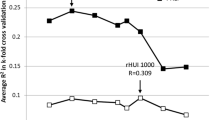

Three independent radiomic features (hereafter shown in italics) differentiated well between responders (sFRLV hypertrophy by ≥ 1.33) and non-responders (sFRLV hypertrophy by < 1.33), as shown in Fig. 3a.

a Independent radiomic features of the baseline CT differentiated well between responders and non-responders to PVE. One feature each was identified for the liver, spleen and bone marrow. b ROC analysis of the resulting model based on all three radiomic features. Best operating point was set to a sensitivity of 1, resulting in a specificity of 0.5. c The decision curve shows that the radiomics-based model had a higher overall net benefit compared with scenarios in which no prediction model was used across the range of threshold probabilities (30–81%), considering a threshold probability of 66% for reaching an sFRLV hypertrophy of ≥ 1.33, as observed in our study cohort. CT Computed tomography, PVE Portal vein embolization, sFRLV Standardized future remnant liver

Larger values of MaximumProbabilityliver and TotalEnergybone, and lower values of Skewnessspleen resulted in a higher probability of responding to PVE. Thus, one feature each per segmented region independently discriminated between responders and non-responders to PVE, as correlation analysis revealed (electronic supplementary Fig. 1a).

When assessing the predictive value of this model, the ROC analysis for the discrimination of responders and non-responders revealed accuracy with an AUC of 0.875 (Fig. 3b). Since PVE is an interventional procedure preceding major hepatectomy as mostly the only remaining curative option in patients with primary or secondary liver cancer, a model for sFRLV hypertrophy prediction must avoid the exclusion of patients from PVE who would have shown sufficient hypertrophy and who thus would have been eligible for surgery and curative treatment. Therefore, the best operating point of the model at the ROC was set to a sensitivity of 1, resulting in a best operating point at 0.4 (Fig. 3b), with a specificity of 0.5, a positive predictive value (PPV) of 0.769 and a negative predictive value (NPV) of 1.

The radiomics signature was built according to multivariate logistic regression analysis.

Here, the corresponding values for MaximumProbalityliver, Skewnessspleen, and TotalEnergybone were inserted for each patient of the validation dataset. The optimal model-derived cut-off (best operating point = 0.4) (Fig. 3b) was applied to the validation dataset to perform stratification for responding to PVE:

Decision curve analysis can assess the effectiveness of the created model regarding clinical utility by determining the net benefit. In addition, considering a threshold probability of 66% for reaching an sFRLV hypertrophy of ≥ 1.33, as observed in our study cohort, decision curve analysis showed that the radiomics-based model had a higher overall net benefit than the no-prediction model (i.e., treat all or treat none scheme) in predicting sFRLV hypertrophy across the range of threshold probabilities between 30 and 81%.